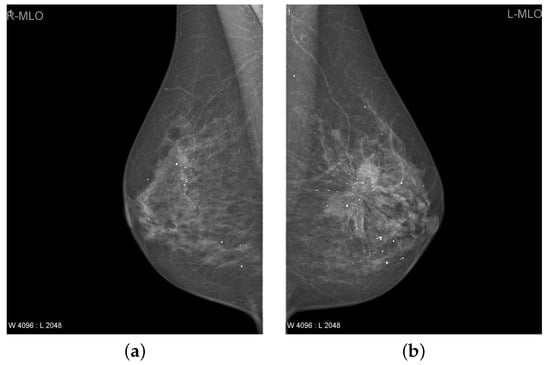

In the breast, cancer cells can increase to the lymph nodes and affect other body parts, i.e., lungs. Breast cancer usually begins with ductal dysfunction (invasive ductal carcinoma). Although, it can also originate in glandular tissues and other cells called lobules and breast tissue [15]. The researchers also found that changes in hormones, lifestyle, and the environment also increase the risk of breast cancer [16,17]. Low dose X-ray examination of the breast is utilized to envisage the internal structure of the breast. This process is medically called mammography. This is evaluated as the best suitable approach for the detection of breast cancer. Compared to previously used equipment, mammography shows the breast to a much lower radiation dose [18]. It is one of the most reliable screening tools and has been shown to be a significant approach for early breast cancer detection in recent times [19]. A mammogram of each breast was recorded in two different views, namely the medial-lateral oblique (MLO) view and the cranio-caudal (CC) view as shown in Figure 1. Estimated new cases recorded in 2021 were 281,550 and the percentage of all the new cancer cases was 14.8% in the U.S. The estimated deaths in 2021 was around 43,600 having a percentage of 7.2%. The 5-year relative survival rate of breast cancer from 2014 to 2019 was 92.16% in the U.S [20].

Figure 1.

The breast mammogram of a patient [21]. (a,b) Right and left medial-lateral oblique (MLO) view, (c,d) Right and left cranio-caudal (CC) view.